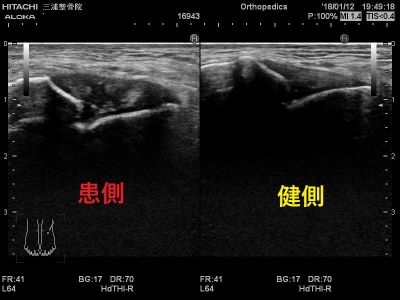

当院では、足関節捻挫が疑われる患者様が来院された際は、視診や触診を起こなったうえでエコーにて患部の状態を確認します。足関節捻挫の可能性が疑われる場合は、炎症を抑える立体動態波を行い、疼痛の緩和します。